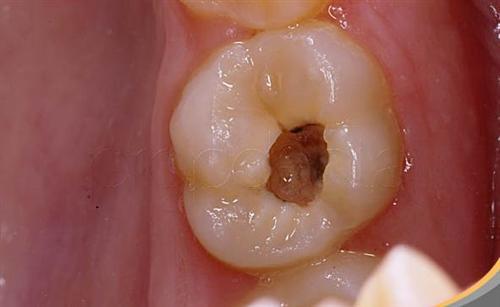

當(dāng)齲齒發(fā)展到較為嚴(yán)重的程度,爛到神經(jīng)時,會給患者帶來較大的痛苦和困擾。許多人會面臨是否需要殺神經(jīng)等一系列問題。本文將深入探討齲齒爛到神經(jīng)后的相關(guān)情況和應(yīng)對方法,幫助大家更好地了解和應(yīng)對這一狀況。

一、齲齒爛到神經(jīng)的癥狀表現(xiàn)

劇烈疼痛

這是最明顯的癥狀之一,尤其在受到冷熱刺激或咬合時,疼痛可能會非常劇烈,甚至難以忍受。有研究表明,約70%的患者在齲齒爛到神經(jīng)時會出現(xiàn)明顯的疼痛癥狀。

自發(fā)痛

即使沒有外界刺激,牙齒也可能會出現(xiàn)自發(fā)性的疼痛。

夜間疼痛加劇

夜間時疼痛可能會更加明顯,影響睡眠質(zhì)量。